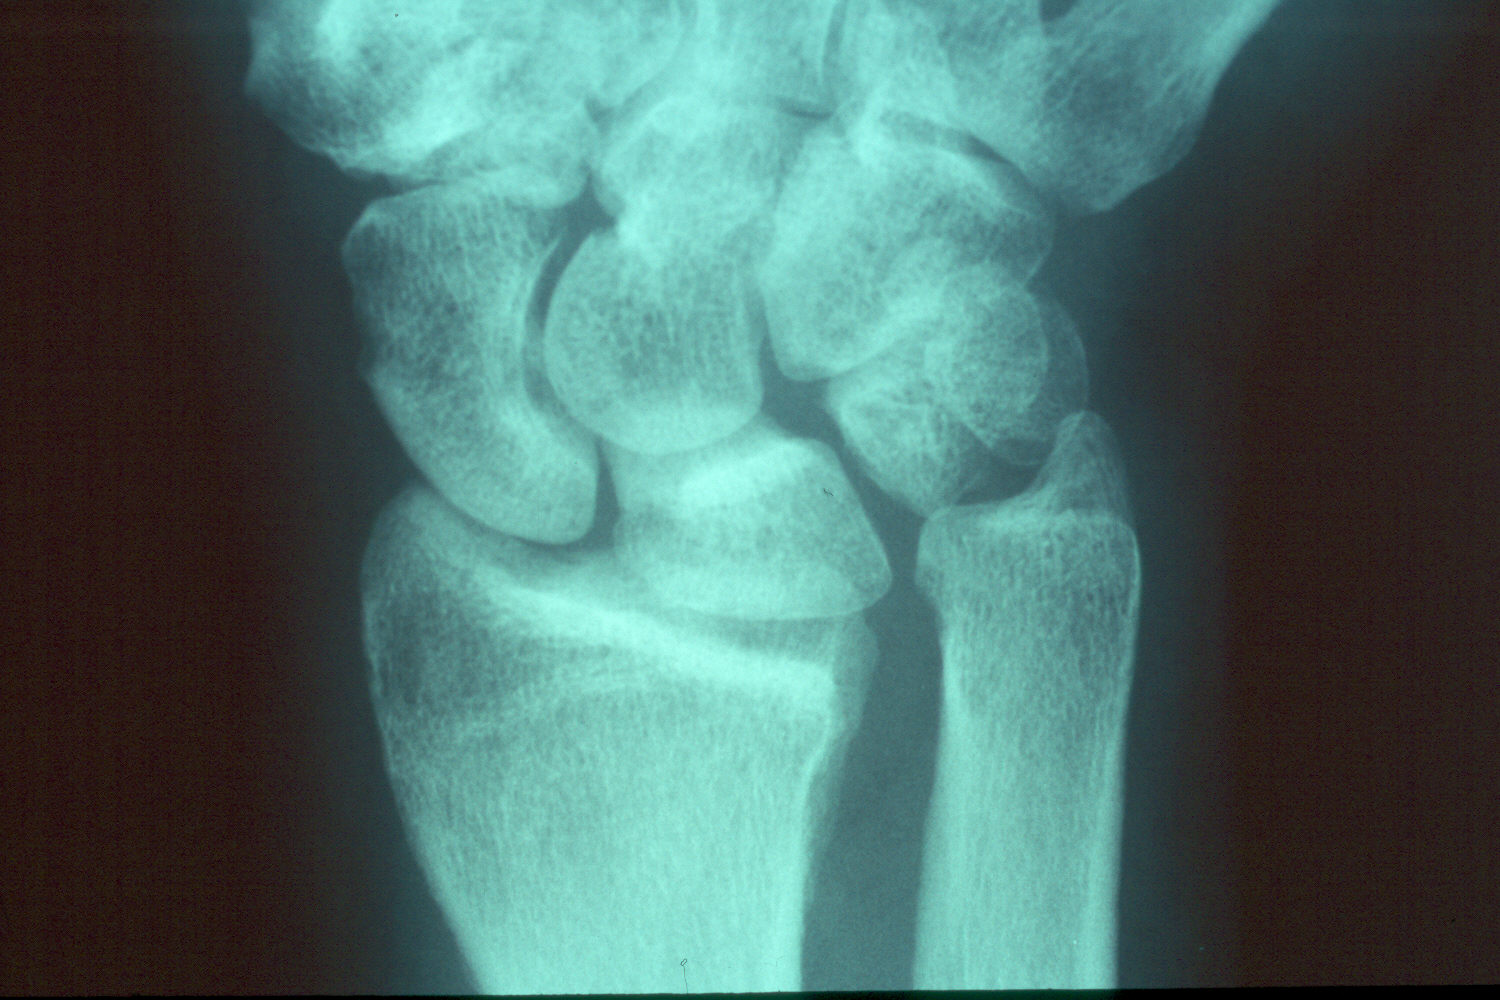

This patient had undergone a radial head excision as primary treatment for his radial head fracture.

Prior radial head excision.